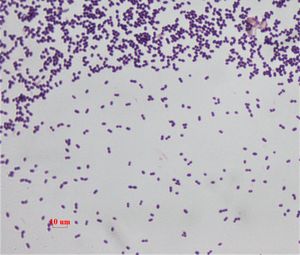

''엔테로코커스 패칼리스''(Enterococcus faecalis, E. faecalis)는 운동성이 없는 세균으로, 다양한 감염을 유발할 수 있으며 항생제 내성을 나타내는 경우가 많다. 생리학적으로는 다양한 에너지원을 대사하고 극한 환경에서도 생존하며, 병원성 관련 독성 인자를 가지고 있다. 다양한 항생제에 내성을 보이며, 특히 반코마이신 내성이 문제가 된다. 치료를 위해 여러 약물 조합이 연구되고 있으며, DNA 복구, 생물막 형성 등의 특징을 갖는다. 또한, 수질 지표로 사용되기도 하며, 인간 배출이 수역 오염의 원인이 될 수 있다.

''E. faecalis''는 운동성이 없는 미생물이다. 가스를 생성하지 않고 포도당을 발효시키며, 과산화수소와 함께 카탈레이스 반응을 일으키지 않는다. 리트머스 우유를 환원시키지만, 젤라틴은 액화시키지 않는다. 통성 혐기성 세균으로 영양 배지에서 일관된 성장을 보인다. 글리세롤, 젖산, 말산, 구연산, 아르기닌, 아그마틴 및 많은 케토산을 비롯한 다양한 에너지원을 대사한다. 엔테로코커스(Enterococci)는 극한의 알칼리성 pH (9.6) 및 염 농도를 포함한 매우 혹독한 환경에서도 생존한다. 이 세균은 담즙산(bile salts), 세제, 중금속, 에탄올, 아지드 및 건조에 견딘다. 10~45°C 범위에서 생장할 수 있으며, 60°C에서 30분간 생존할 수 있다.[42]